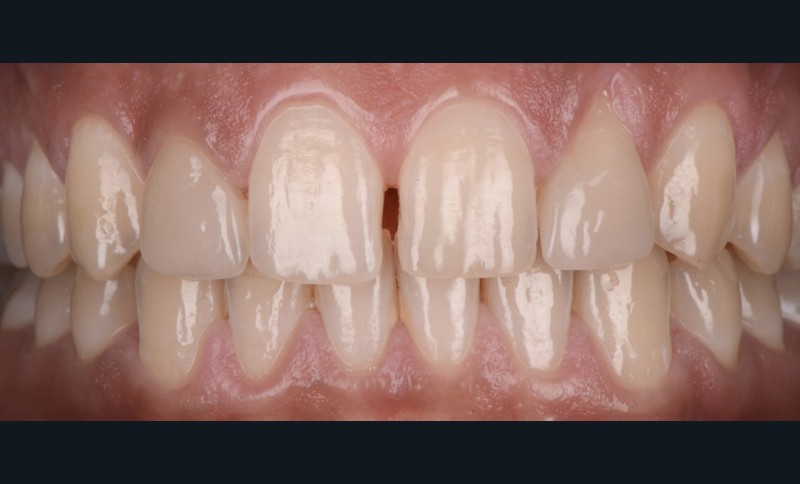

L’analyse esthétique montre notamment (fig. 1 et 2) :

- un ratio des incisives centrales de 78 % ;

- un diastème inter-incisif de 1 mm considéré comme disgracieux par la patiente ;

- un décalage des collets de 12 et 22 ;

- un défaut de teinte des facettes existantes sur 12 et 22.